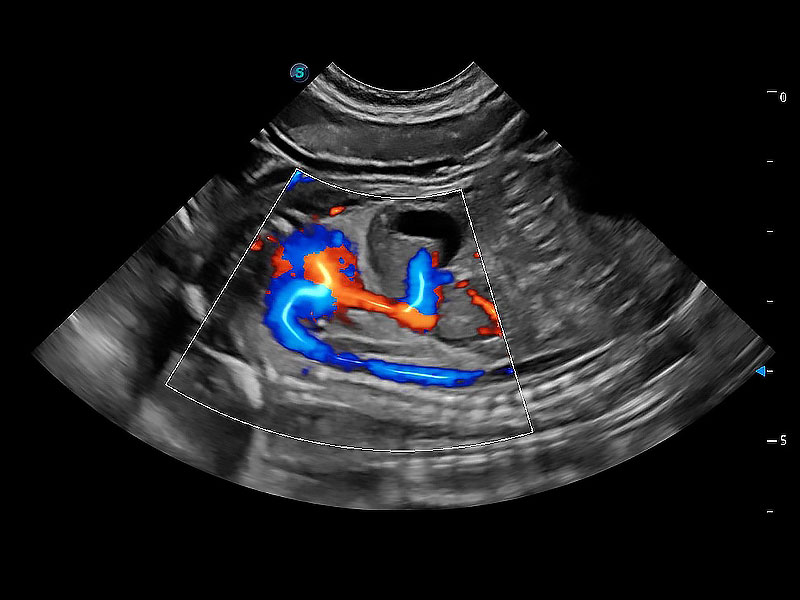

非线性融合造影成像充分利用谐波和基波信号,为难以观察的血流进行增强显像。可用于线阵、凸阵、微凸阵、相控阵探头。

ProPet 80 配备了丰富的心脏探头群、先进的成像技术和专业的心脏测量工具,可帮助动物医生为不同体型和生理结构的动物提供心脏和心肌功能的全面评估。